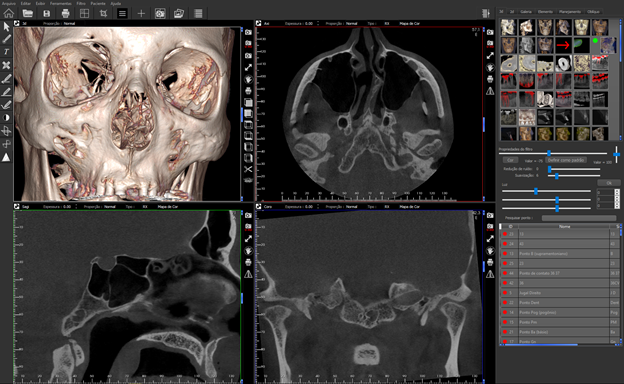

Existem várias publicações que fornecem diretrizes clinicas baseadas em evidências sobre as aplicações desta modalidade de imagem em odontologia. Pequenos e médios volumes do complexo oral e maxilo-facial adquiridos em alta resolução fornecem capacidade diagnósticas superiores em comparação com a imagem 2D convencional em várias situações clínicas. Estes incluem a exibição de estruturas anatômicas-chave e sua relação com a dentição, visualização da morfologia dentária sem sobreposição, avaliação do dente e degenerescência óssea, planejamento cirúrgico e avaliação do resultado de terapias. É por isso que eu uso o software Evol da CDT. Ele me ajuda a maximizar o diagnóstico de imagem devido a uma variedade de ferramentas que permite a fácil manipulação e melhoramento de imagens de varreduras TCFC. A TCFC sem dúvida nos proporcionou um grande poder em imagens diagnósticas. Com este poder vem uma grande responsabilidade de interpretar os volumes 3D corretamente e na íntegra.

A responsabilidade de identificar resultados incidentais em volumes TCFC não deve ser baseada no medo de responsabilidade e negligência. É no melhor interesse do paciente, bem como o provedor de reconhecer os achados incidentais como muitos têm o potencial para mudar um plano de tratamento. Desenvolver um método sistemático e reproduzível para analisar volumes pode melhorar a produtividade e melhorar o tempo de interpretação diagnóstica. O software Evol tem muitas ferramentas para maximizar a interpretação e minimizar o tempo de interpretação TCFC. Depois de uma imagem é adquirida o software Evol é a minha escolha para ajuste e navegação nos dados. É imperativo que os radiologistas relatem todas as suas descobertas de interpretação (primária e incidental) no relatório do paciente. Esta é apenas a primeira etapa da interpretação radiológica, que é reconhecer normal versus variação anatômica e patologia. Em segundo lugar, o diagnóstico diferencial para tais achados incidentais.

Uma tomografia da maxila foi adquirida para avaliação do dente 21 e dos dois seios maxilares. Durante a interpretação do exame foi notado uma área ovalada, multilocular grande, bem definida, corticalizada na região retroclival prepontine. Este achado é fortemente consistente com Ecchordosis Physaliphora. Ecchordosis physaliphora é uma lesão hamartomatosa benigna congênita e pode ser encontrada em qualquer lugar da base do crânio ao osso sacrum. Também notei um forame jugular assimétrico no lado direito. Note que as margens são corticalizadas e não há sinais ou erosão / padrão mordida de traça. O aumento do forame jugular tornando-o assimétrico é fortemente consistente com Bulbo Jugular Alto. Esta variante anatômica ocorre mais comumente do lado direito. Há uma grande e fina espora óssea decorrente da parede lateral esquerda do septo nasal estendendo todo o caminho até a parede lateral esquerda da cavidade nasal.